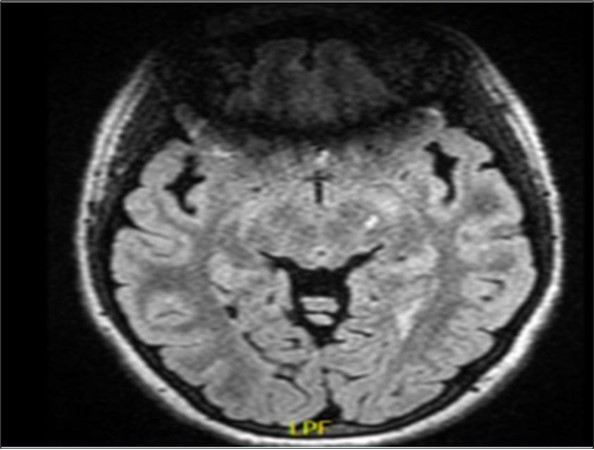

She was doing very well on treatment, until this presentation, when she presented acutely with left third cranial nerve palsy. Due to this atypical presentation MRI with MR angiogram (MRA) of the brain were performed with additional thin cuts over the exit of the third cranial nerve and showed no evidence of any aneurismal lesion or a mass lesion. However, there was an increase in the size of a previously present left midbrain lesion (See Figure 1).

Figure 1.showing a left midbrain demyelinating lesion on a fluid attenuated inversion recovery (FLAIR) image. To note, there is an artifact anteriorly because of the presence of teeth orthodontics.